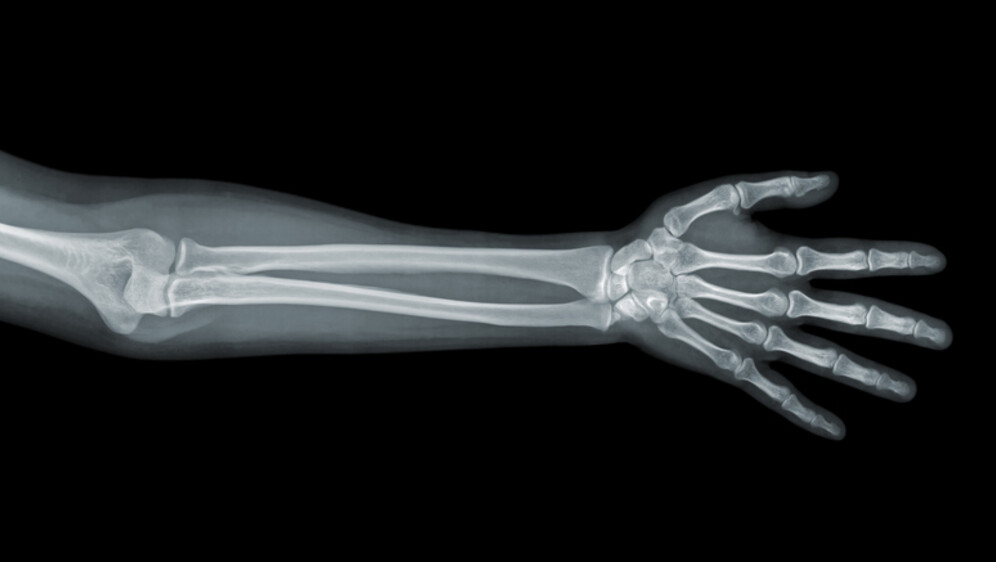

Znanstvenici su utvrdili da je izloženost PFOA bila povezana s nižom gustoćom kostiju podlaktice u dobi od 12 godina, dok su ostale PFAS tvari pokazivale učinke koji su ovisili o vremenu izloženosti.